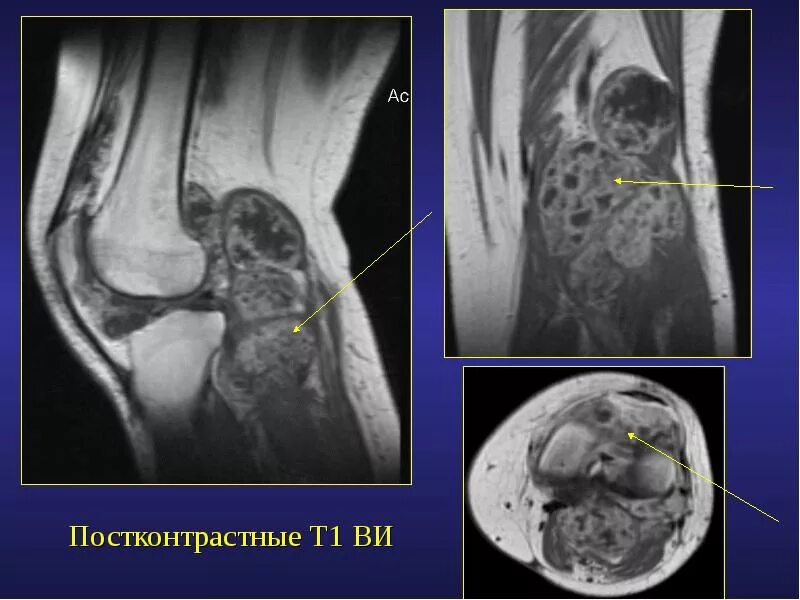

Саркома мрт